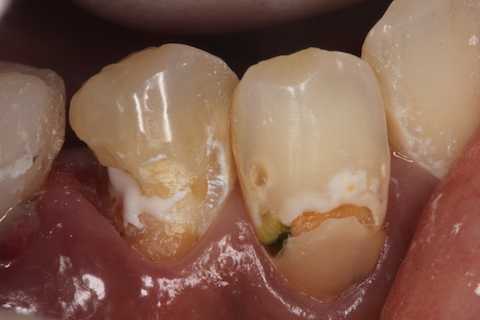

残根上のCR8 2025.10.28